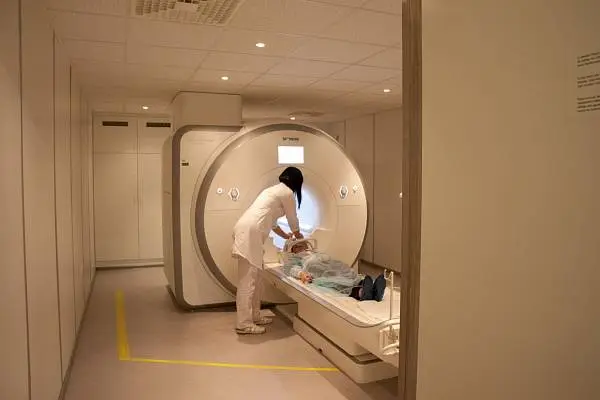

Как проходит МРТ головного мозга с контрастом?

Процедура проводится амбулаторно, в специально оборудованном кабинете клиники. Во время сканирования не применяется рентгеновское излучение, поэтому исследование не приносит никакого вреда организму и при необходимости может повторяться каждую неделю. -